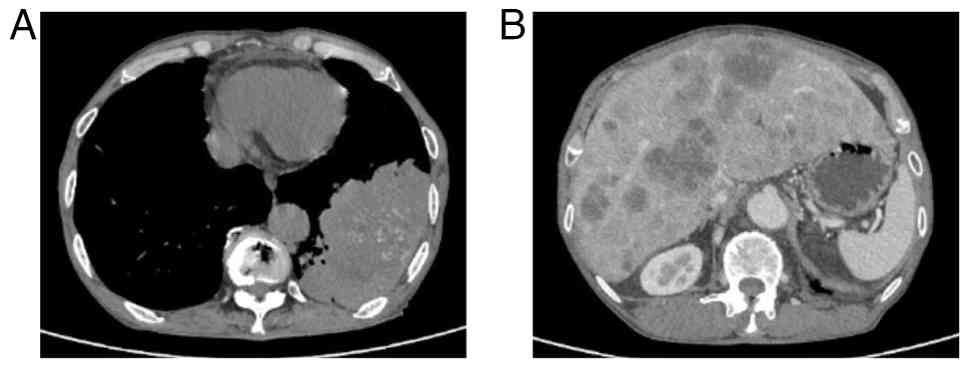

In June 2024, a 74-year-old man was admitted to Huai'an Hospital Affiliated to Yangzhou University and The Fifth People's Hospital of Huai'an (Jiangsu, China) with symptoms of coughing, hemoptysis, decreased appetite and abdominal distension. The patient had a history of chronic obstructive pulmonary disease spanning over 20 years. Computed tomography (CT) identified a 12.3-cm soft-tissue mass in the left lower lobe of the lung, with multiple metastatic lesions noted in the liver (Fig. 1). A biopsy of the lung lesion under CT control was performed. Tissues were fixed in 10% neutral formalin solution at room temperature for 24 h, then dehydrated and embedded in paraffin. The tissues were sliced into 5-µm thick sections. Immunohistochemical analysis was performed using the EnVision two-step method. Both primary and secondary antibodies were ready-to-use antibodies purchased from Henan Celnovte Biotechnology Co., Ltd. The following antibodies were employed: CK5/6 (clone C6H1/C1C8; catalog no. CCM-0983), p40 (clone C3B4; catalog no. CPM-0133), p53 (clone C2H10; catalog no. CPM-0142) and Ki-67 (clone C3G4; catalog no. CKM-0032). All staining was performed using an automated immunohistochemical staining machine (catalog no. CNT360-M2; Henan Celnovte Biotechnology Co., Ltd.), according to the manufacturer's instructions. All section observations and image acquisition were performed using a light microscope (ECLIPSE Ci-S; Nikon Corporation). Immunohistochemical analysis of the tissue sample revealed positive expression of CK5/6, p53 and p40, and the Ki-67 index was 30% (Fig. 2). Based on clinical presentation, imaging studies and pathological findings, the patient was diagnosed with primary lung squamous cell carcinoma. The patient refused a liver biopsy and programmed death ligand 1 testing. The patient was diagnosed with squamous cell carcinoma of the left lower lung lobe and liver metastasis, cT4N3M1c, clinical stage IVB, according to the American Joint Committee on Cancer 8th edition (13). The patient received intravenous sintilimab (200 mg on day 1) and albumin-bound paclitaxel (200 mg on day 1 and 100 mg on day 8) plus cisplatin (30 mg on days 1–3) of each 21-day cycle for 4 cycles. In October 2024, the patient showed a significant reduction in measurable lesions with regard to both the primary tumor and liver metastasis. The mass in the lower lobe of the left lung decreased from 12.3 to 8.4 cm in diameter, while the largest liver metastasis shrank from 3.8 to 1.5 cm in diameter, with some liver metastases disappearing (Fig. 3). Following the aforementioned four cycles of sintilimab and albumin-bound paclitaxel plus cisplatin, the patient continued maintenance therapy with sintilimab (200 mg on day 1 of each 21-day cycle). Tumor status was assessed every 6 to 8 weeks. The assessment included CT scans of the chest, abdomen and pelvis. In June 2025, CT demonstrated a nodular contour of the liver with capsular retraction, mild ascites, and esophageal and gastric varices (Fig. 4). The patient had no history of alcohol consumption. Laboratory tests indicated negative or normal results for all causes of liver disease, including serological tests for hepatitis B and C, and serological tests for autoimmune conditions. The patient refused to undergo a liver biopsy. The patient's alanine aminotransferase level was 57 U/l (normal range, 9–50 U/l), aspartate aminotransferase was 55 U/l (normal range, 15–40 U/l), γ-glutamyl transferase was 185 U/l (normal range, 15–40 U/l), total bilirubin was 27.9 µmol/l (normal range, <26 µmol/l) and albumin was 29.4 g/l (normal range, 40–55 g/l). The patient underwent abdominal paracentesis, with large-volume drainage of ascites, diuretic therapy and infusion of human albumin (once daily, 10 g per dose) as part of active treatment. Over the next 2 months, the Eastern Cooperative Oncology Group (http://ecog-acrin.org/resources/ecog-performance-status/) performance status gradually worsened. In August 2025, the patient ultimately succumbed to hepatic failure.

(A) Computed tomography scans showing

a 12.3-cm lung lump in the left lower lobe. (B) CT of the liver

after contrast enhancement showing numerous liver metastases.

Figure 1.

(A) Computed tomography scans showing a 12.3-cm lung lump in the left lower lobe. (B) CT of the liver after contrast enhancement showing numerous liver metastases.